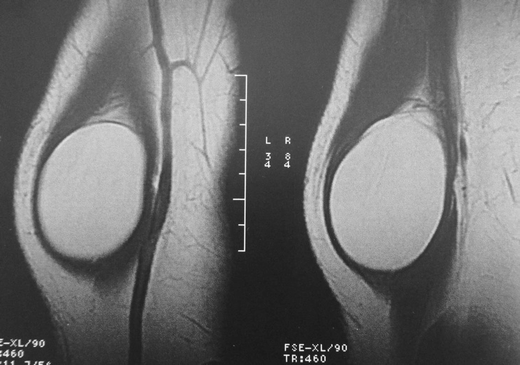

T1 MRI images, showing an intramuscular mass on the supinator muscle

The diagnosis of PINS is based on clinical history and physical examination and is confirmed by electrophysiological studies. Classically, this syndrome has neither pain nor other sensory symptoms, but there are cases of forearm pain and paralysis of the extensor muscles of the forearm. If there is any suspicion, based on clinical examination, of a mass as the causative factor of PINS, MRI scan is the imaging method of choice for evaluating their presence and extent. In this clinical case, however, the lipoma was located intramuscularly, and there was a palpable mass on the forearm.